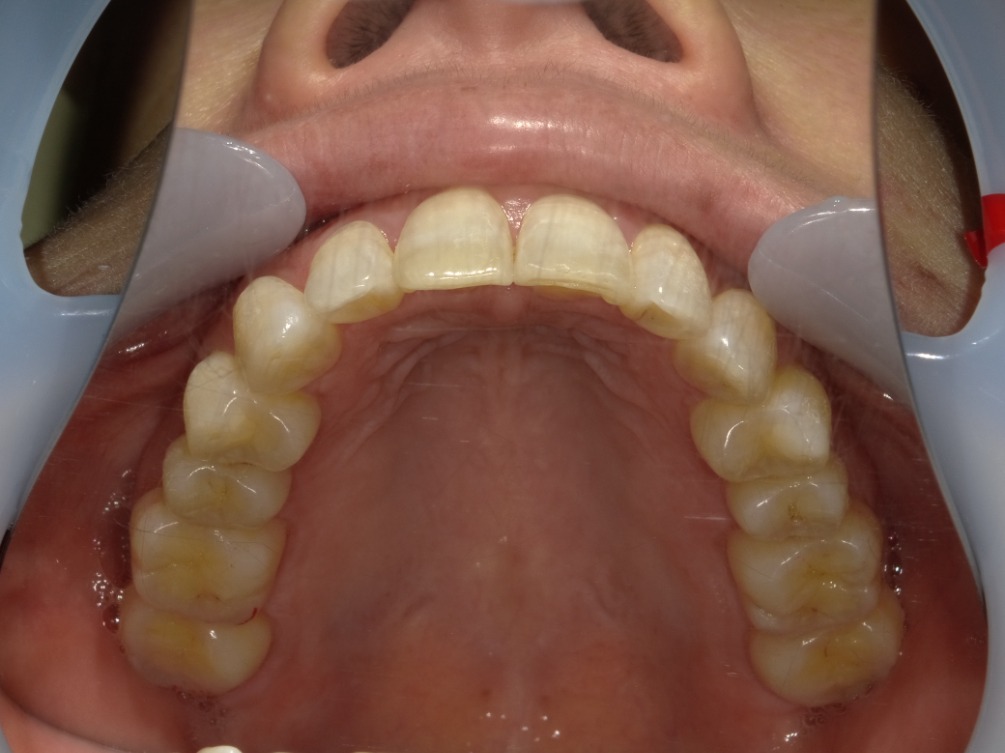

AFTER

上顎